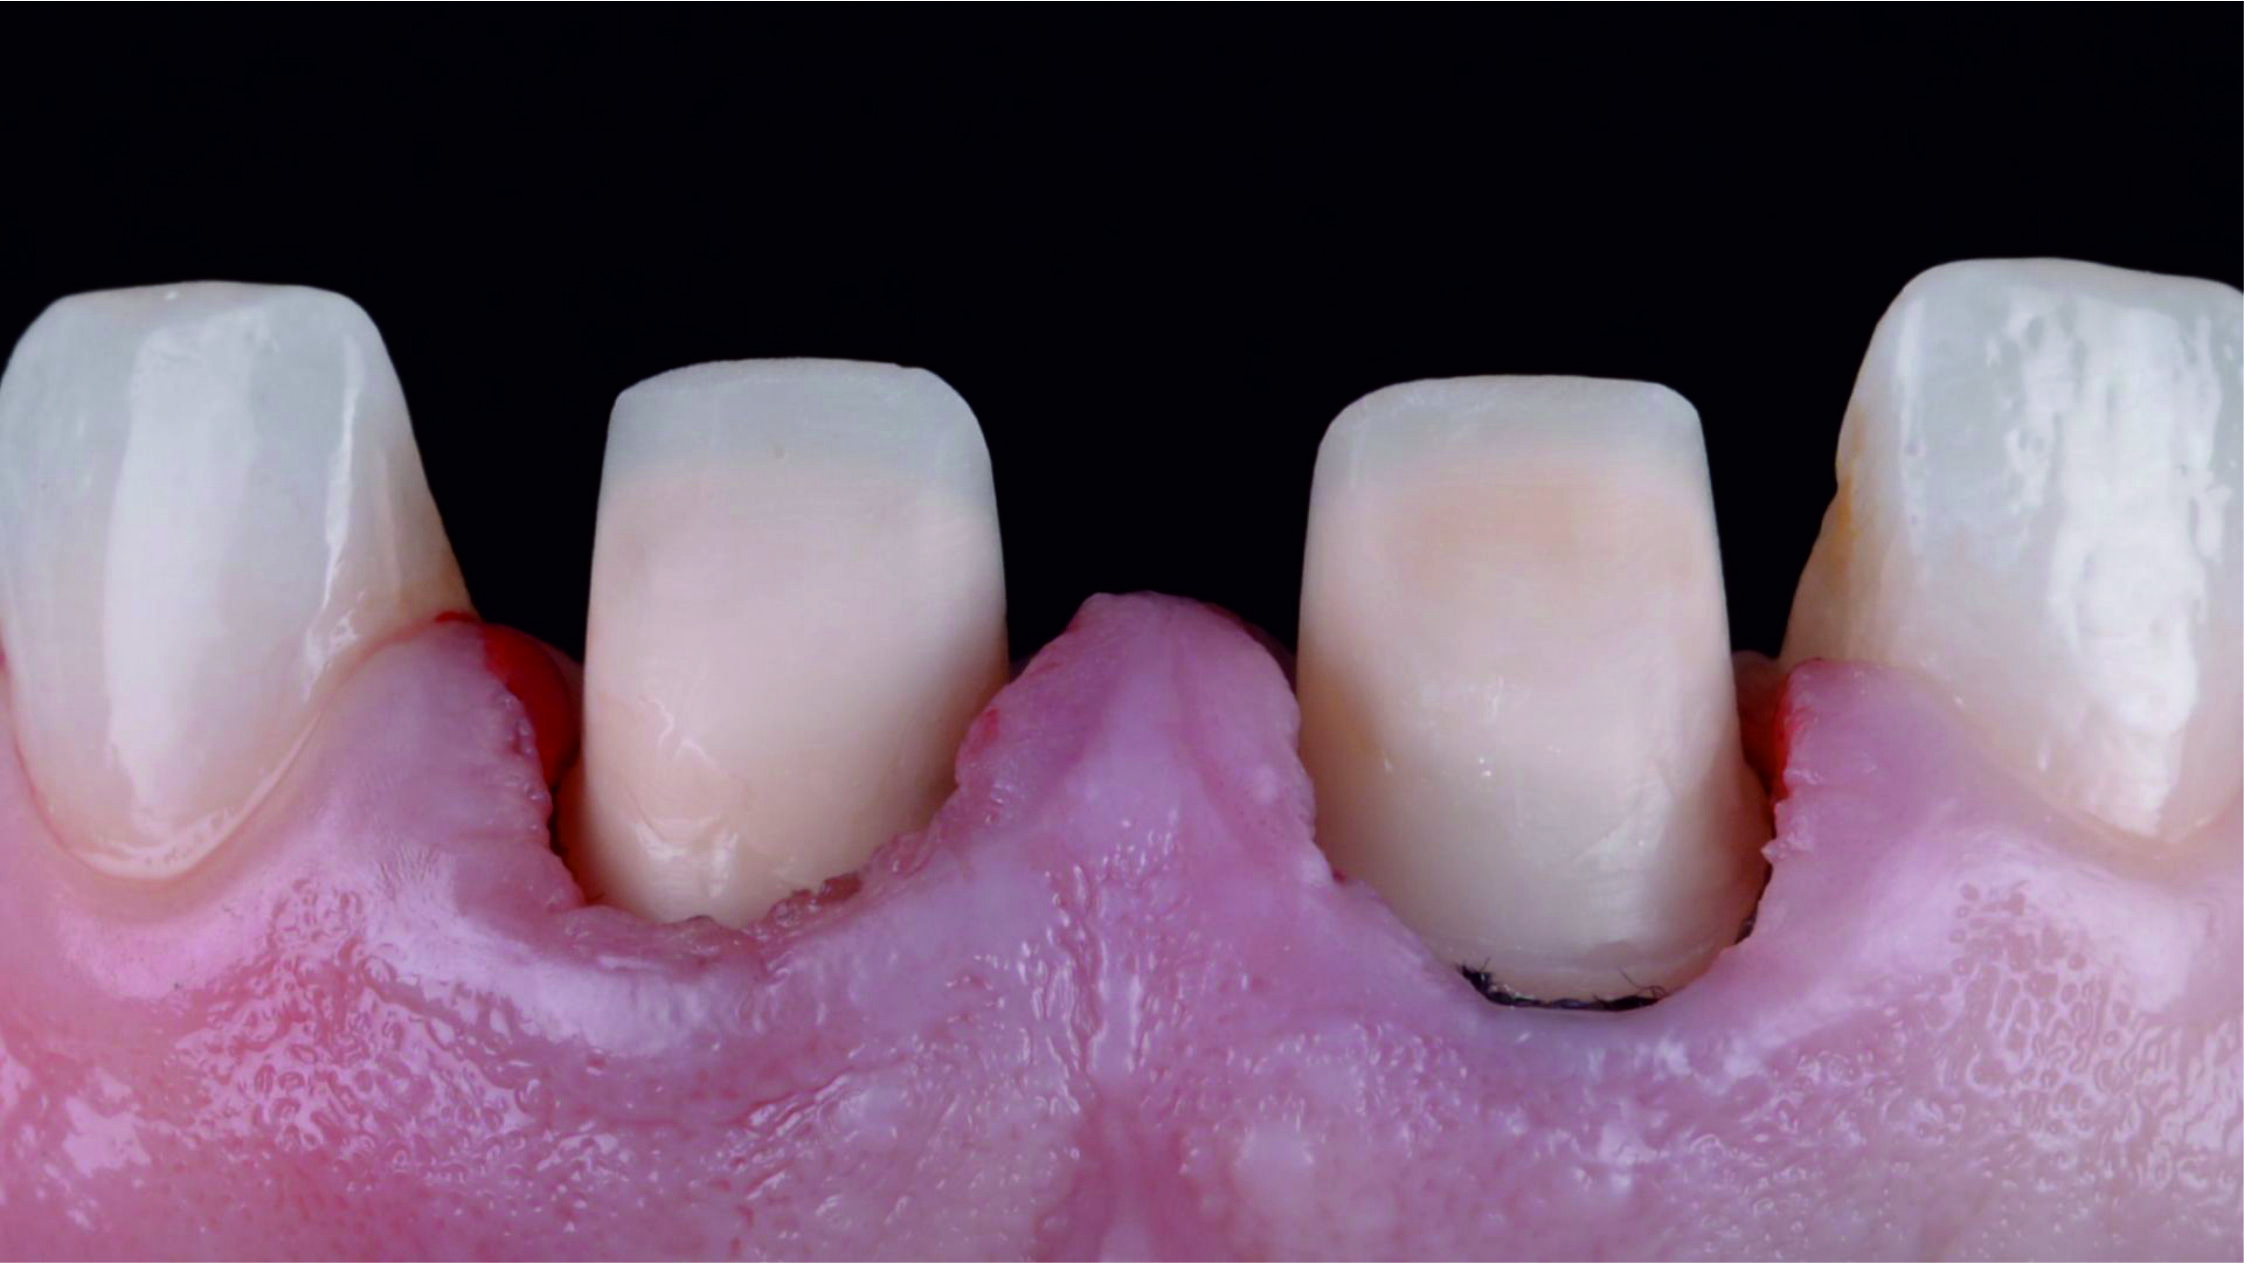

Фото 8. Після видалення штучних коронок видно, що кукси відпрепаровані з надлишком.Фото 9. Після усунення цементу, який залишився, та установки ретракційної нитки можна розглянути під’ясенну зону препарування, яка має різну глибину занурення, значно більше виражену в проксимальних ділянках кукс.